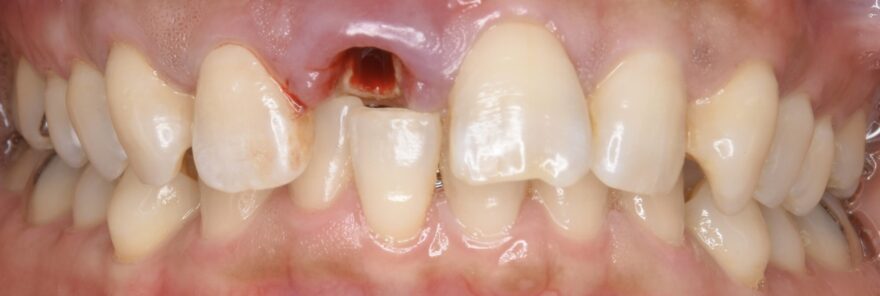

初診時口腔内写真

左側の差し歯が壊れてしまい、当院を受診されました。

歯根はとても小さく、顕微鏡治療でも残せないと判断しました。